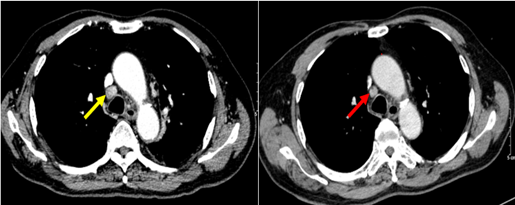

- Chụp cắt lớp vi tính ngực (tháng 9/2024)

Hình 2: Hình ảnh hạch trung thất nhóm IV (mũi tên vàng) kích thước 11*18mm, bờ tròn đều, mất cấu trúc rốn hạch

Hình 7.1: Cắt lớp vi tính ngực ở cửa sổ nhu mô

Hình 7.2: Hình ảnh cắt lớp vi tính ngực ở cửa sổ trung thất

Kết luận: Hình ảnh chụp cắt lớp vi tính ngực: sau 6 đợt điều trị khối u (vòng tròn đỏ) giảm kích thước từ 72x41mm (bên trái) xuống còn 43x28mm (bên phải)

Hình 8: Hình ảnh CT ngực: Sau 6 đợt điều trị hạch trung thất giảm kích thước từ 11x18mm trước điều trị (mũi tên vàng) xuống còn 8x10mm sau điều trị (mũi tên đỏ)